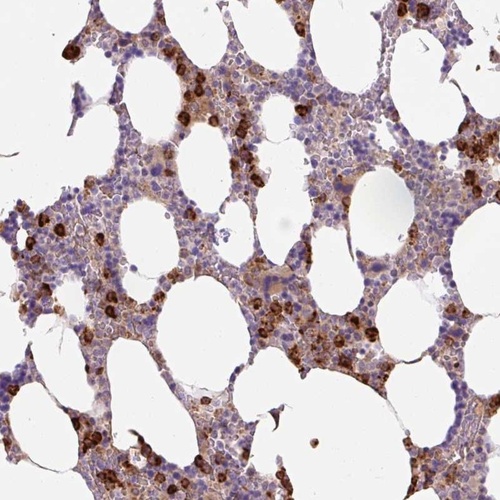

Immunohistochemical staining of human bone marrow shows strong cytoplasmic positivity in subset of hematopoietic cells.